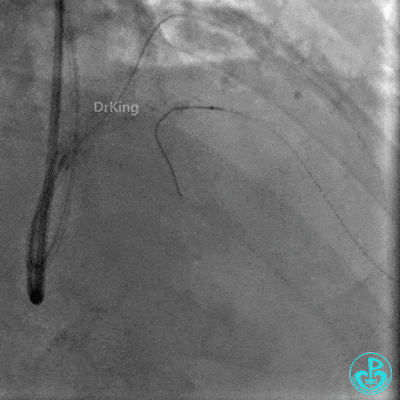

启动Reverse CART,正向2.0×15mm球囊扩张后逆向导丝尝试进入前降支近端真腔。

正向Guidezilla迎合,逆向导丝、微导管进入子导管,正向导丝通过逆向微导管后2.0×15mm球囊扩张闭塞段。

前降支串联植入2.5×30mm、3.0×30mm支架,对角支导丝保护。